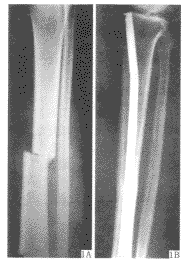

【摘要】 目的 介绍折弯髓内钉治疗胫腓骨骨折的方法与疗效。方法 将V形钉或梅花钉两端折弯治疗胫腓骨骨折45例。结果 随访6个月~5年,平均2年,除2例延迟愈合外,43例术后半年内获骨性愈合,膝踝关节功能良好。结论 该方法可为骨折愈合创造有利的力学环境,维护骨折部的血运,减少术后感染,是治疗胫腓骨骨折理想方法之一。